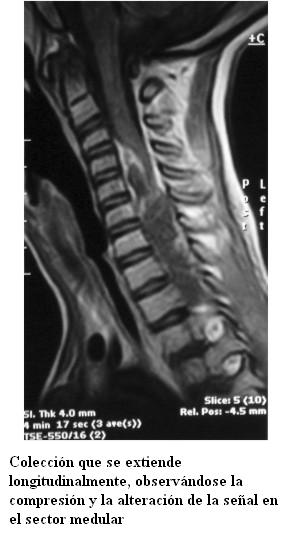

Tomografía de cráneo normal. Hemocultivo estéril.

Se traslada al Centro Hospitalario Pereira Rossell. Se realiza resonancia magnética de raquis que muestra un proceso patológico a nivel cérvico-torácico intrarraquídeo extramedular, que se extiende desde la tercera vértebra cervical hasta la primera torácica (figura 1). Con el diagnóstico de empiema raquídeo se inicia tratamiento con vancomicina, metronidazol y ceftriaxona con buena evolución inicial. Sin embargo, a los 6 días presenta peoría neurológica con aumento de la paresia de miembro superior izquierdo a predominio distal. A nivel de miembros inferiores hiperreflexia, clonus y Babinski bilateral. Se repite resonancia magnética que muestra aumento de la colección epidural comprometiendo hasta la cuarta vértebra torácica (figura 2). Se realiza hemilaminectomía de quinta vértebra cervical hasta primera torácica, obteniéndose abundante pus, amarillo, inodoro. En el estudio bacteriológico no se obtuvo desarrollo bacteriano. Se continúa tratamiento con ceftriaxona-clindamicina por 10 días. Posteriormente se rota a teicoplanina y rifampicina por 10 días, se suspende rifampicina y se continúa con teicoplanina en días alternos por 10 días más en domicilio, completando las 6 semanas de tratamiento antibiótico.